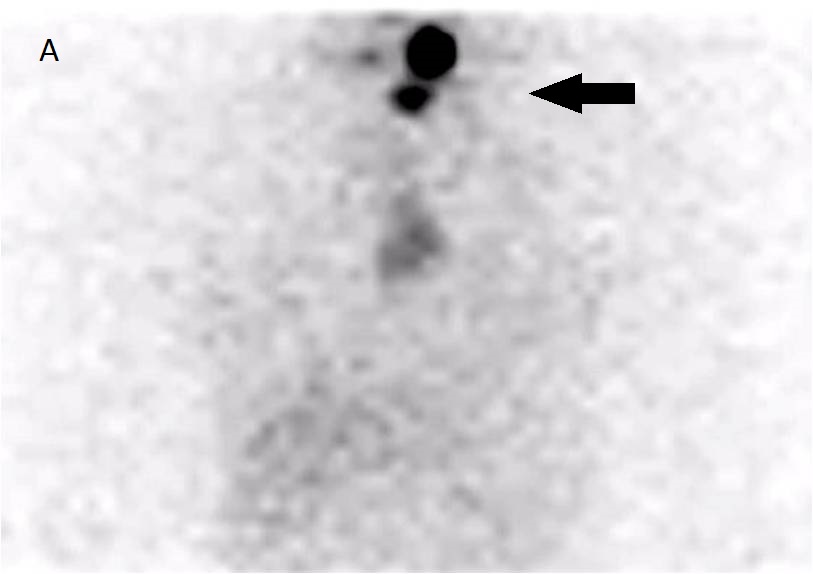

Anterior neck (A) and thoracic (B) views show 3 foci of I-131 uptake probably due to remnant tissue in the thyroid bed (black arrow). Note, Mid Thoracic irregulas uptake, less intense. Spect-CT fusion imagesĀ in (C) and (D) slices, depict anterior localization of the tracer, corresponding to Thymus (yellow arrow).